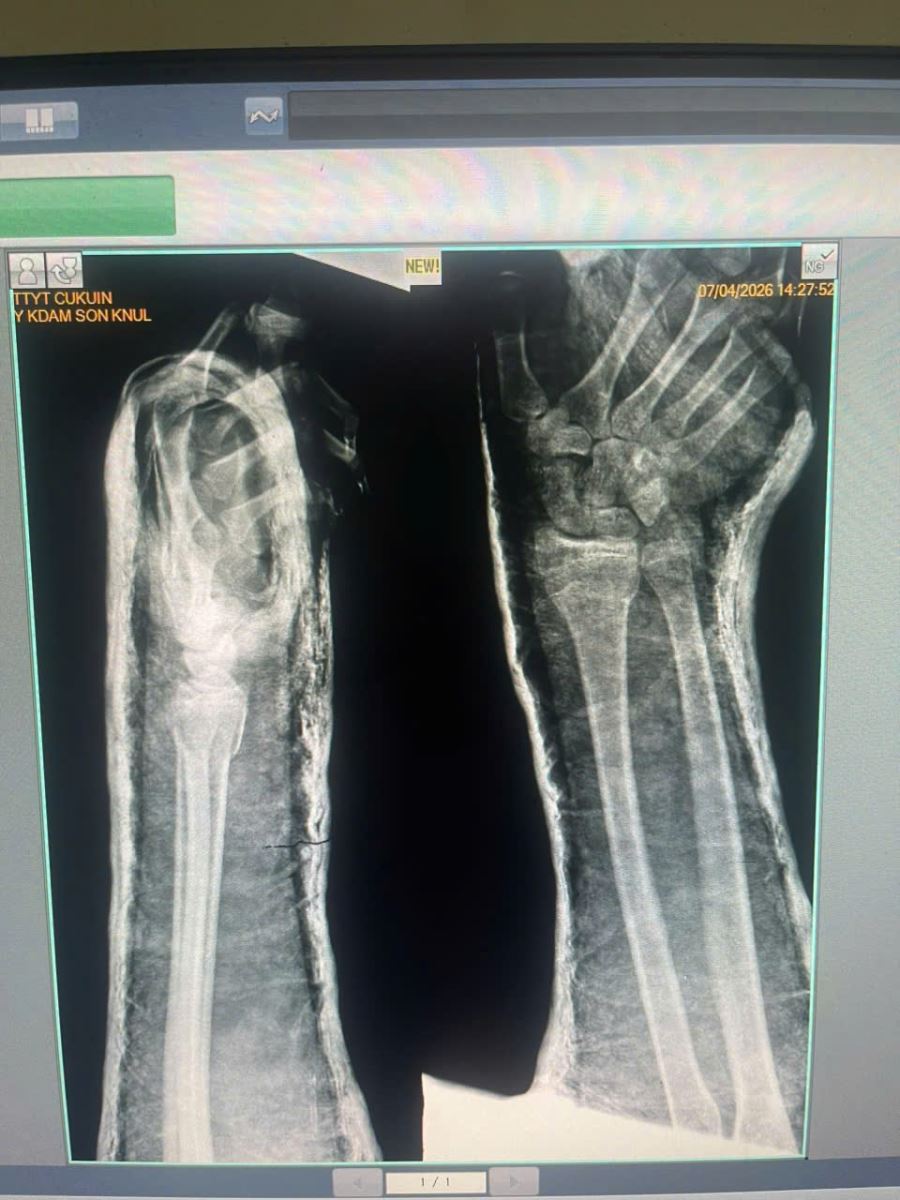

Ngày 7/4/2026 bệnh nhân nam Y.K.S.KL, sinh năm 2009, Buôn Jung B, xã Ea Ktur, Đắk Lắk vào viện với lý do ngã từ độ cao khoảng 3 mét . Bệnh nhân được đón tiếp, thăm khám ngay. Bác sĩ Trịnh Đức Lam, PGĐ trung tâm y tế Cư Kuin trực tiếp khám lâm sàng, chỉ định cận lâm sàng có kết quả. Chẩn đoán: Bệnh nhân gãy kín đầu dưới xương quay trái, trật khớp quay trụ dưới trái + gãy kín xương thuyền trái do tai nạn sinh hoạt.

Bệnh nhân được xử trí nắn, bó bột ngay, kịp thời, kết quả hình ảnh X.quang cho thấy xương trở lại vị trí giải phẫu như bình thường, sức khỏe hiện tại ổn, bệnh nhân được chăm sóc tận tâm.